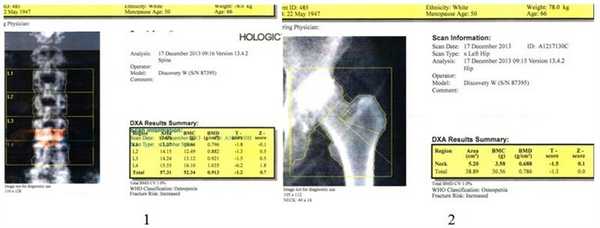

Для оценки минеральной плотности костной ткани (МПКТ) применяли «золотой стандарт» - двухэнергетическую рентгеновскую абсорбциометрию (DEXA) на рентгеновском денситометре Prodigy фирмы «GE LUNAR Corporation» производства Великобритании (рег. № 2002/126, действ. до 12.2013 г.) с использованием кадмий-цинк-теллуридовой детекторной матрицы, на специальном столе. Положение пациента при исследовании - на спине с ротацией стоп кнутри на 15°, определение МПКТ проводили в проксимальном отделе бедренной кости, поясничном отделе позвоночника, по программе «Все тело» (рис. 3).

Рис. 3. Определение МПКТ по стандартным зонам (1 - поясничный отдел, 2 - шейка бедренной кости)

Доза облучения, получаемая пациентом за одно обследование, составляла 0,05 мЗв. Сравнительная оценка полученных результатов производилась по Т-критерию от пиковой костной массы у лиц соответствующего пола в стандартных единицах (SD): Т-критерий до -1SD - норма; Т-критерий от -1 SD до -2,5 SD - остеопения; Т-критерий меньше -2,5 SD - остеопороз.